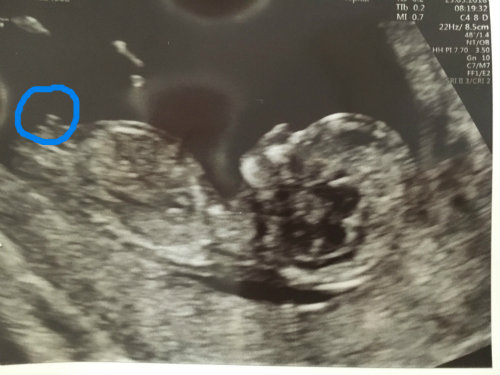

The circled area looks like a boyish nub since it is short and stacked.

dont want to get my hopes up! the other two scans i cant see any boy nub?! but the one you circled it does look stacked - is it definitely not "forked"? i am trying to work out what "three lines" looks like but i cant seem to undertand it either way!